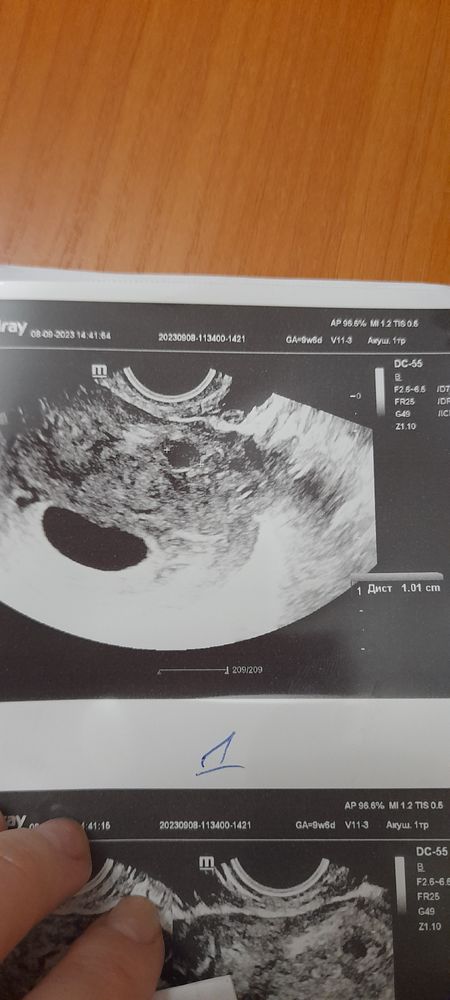

Здравствуйте. Делала узи три дня назад для подтверждения диагноза анэмбриония. Диагноз подтвердили( пустое плодное яйцо 26 мм), но ещё нашли миому 10 мм. Это уже седьмое по счету узи , последнее узи 10 дней назад, но ни на одном узи ничего не находили. И раньше тоже никогда такой диагноз не ставили. Откуда взялась эта миома? И могли ли её с чем-то другим перепутать? Ещё увидели варикозное расширение вен матки... но у меня обострение геморроя и я думаю, что это всё в комплексе, обострение ...